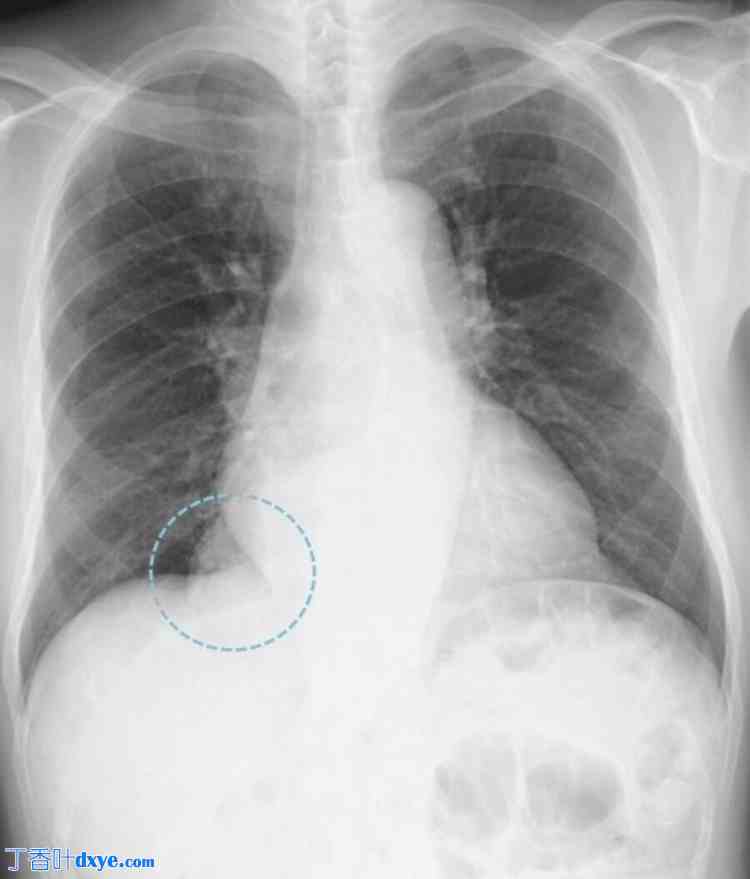

一名79岁的男性患者因胸闷约一个月就诊于当地医院。患者身高169.7 cm,体重70.2 kg。心电图显示心率为65次/分,窦性心律。体格检查未发现胸部和腹部异常。血液检查结果也未发现异常。患者无胃肠道或心血管疾病病史,医生问诊时也未发现腹部或胸部外伤史。然而,患者有糖尿病和血脂异常病史,并定期服药。胸部X光片显示疑似纵隔肿瘤(图1),患者被转诊至呼吸内科。进一步增强MRI(图2)和CT(图3)检查后,由于大网膜血管经食管裂孔延伸至纵隔,怀疑为ITOH,患者被转诊至胃肠外科。患者因症状性疝气接受腹腔镜疝修补术。术中发现食管裂孔右侧为疝口(图 4a),大网膜脱垂至右后纵隔。大网膜未与疝囊粘连,可手法复位至腹腔(图 4b)。

图 3. 增强 CT。

发现腹腔内脂肪经食管裂孔脱垂至纵隔。